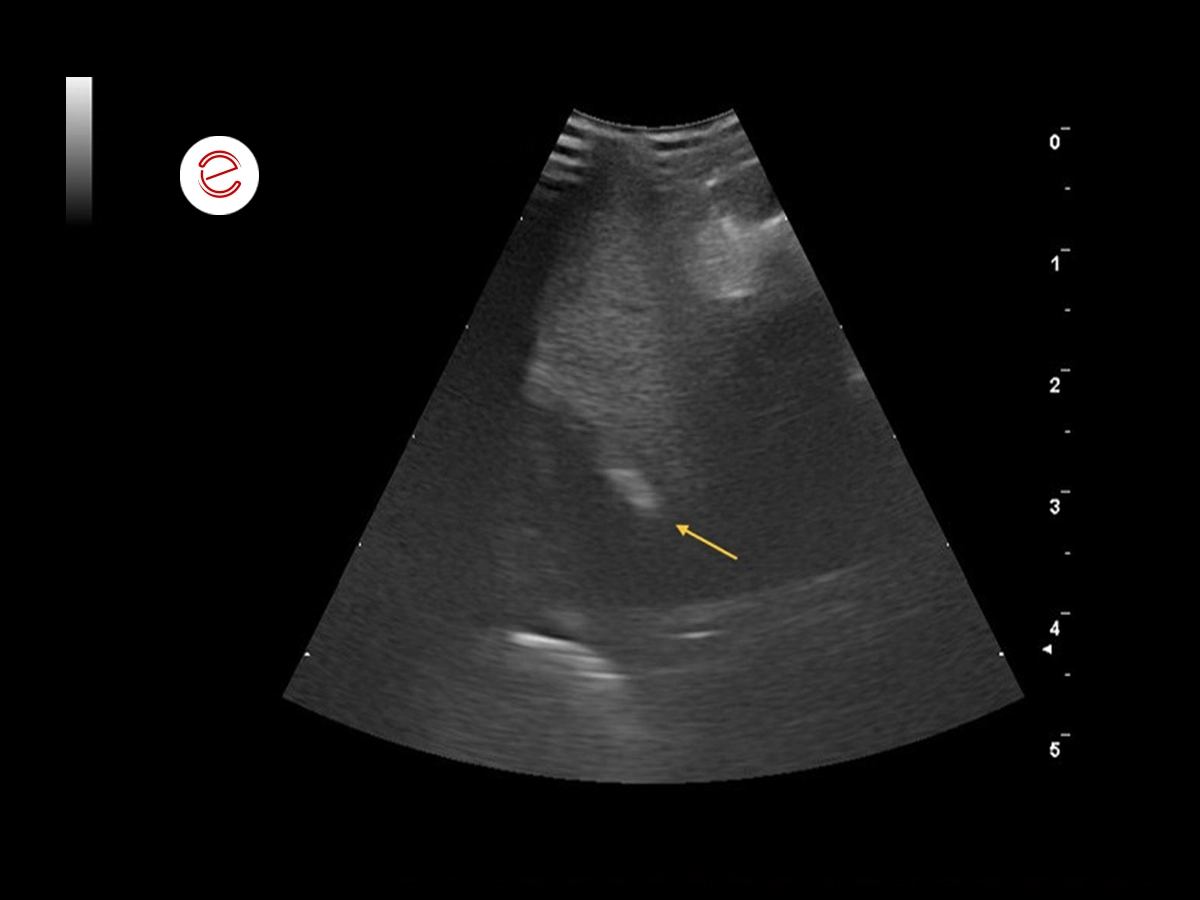

After 2 months of treatment, the bird showed improvement clinically and in the ultrasound examination the mass/granuloma has visibly reduced in size.

The yellow arrow shows the scar tissue that is now present.

The granuloma in the myocardium was an incidental finding. The respiratory disorders resolved within the first few weeks of treatment with antibiotics, hepatoprotection and heart medication. The bird was rechecked monthly until the granuloma resolved after two months, although scar tissue was still visible within the muscle. The suspected cause of the granuloma was a systemic Escherichia coli infection resulting in bacteremia.